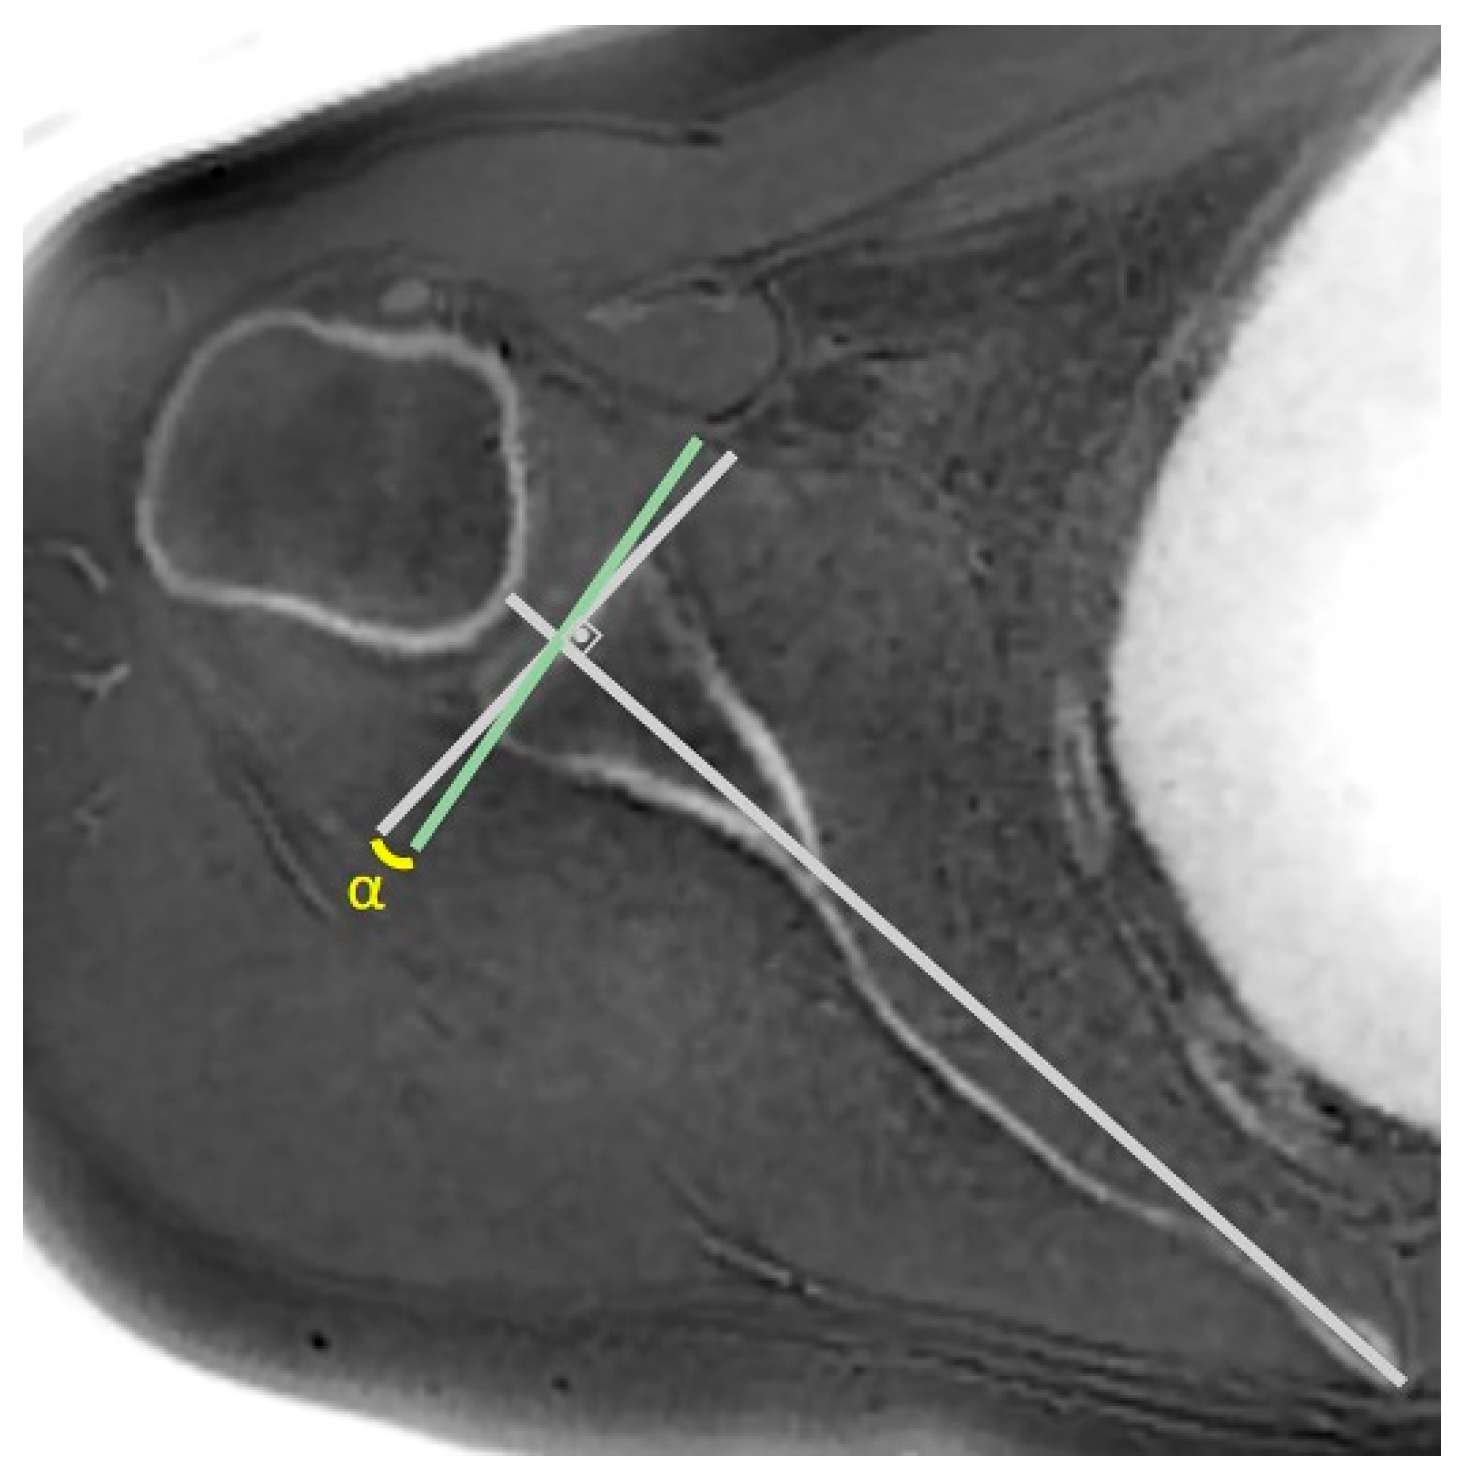

| Critical shoulder angle | 0.914 | 0.838–0.954 | >0.05 | 0.945 | 0.845–0.947 | >0.05 |

| Critical shoulder angle | r | −0.275 | −0.163 | −0.140 | −0.155 | −0.026 | −0.182 |

| p | 0.074 a | 0.296 a | 0.369 a | 0.321 a | 0.869 a | 0.242 a | |

| Critical shoulder angle, degrees (°) | 33.44 ± 4.68 | 31.60 ± 4.71 | 0.392 b |

| Critical Shoulder Angle | 0.914 | 0.93 [52] –0.965 [44] | 0.945 | 0.943 [44] –0.989 [45] |